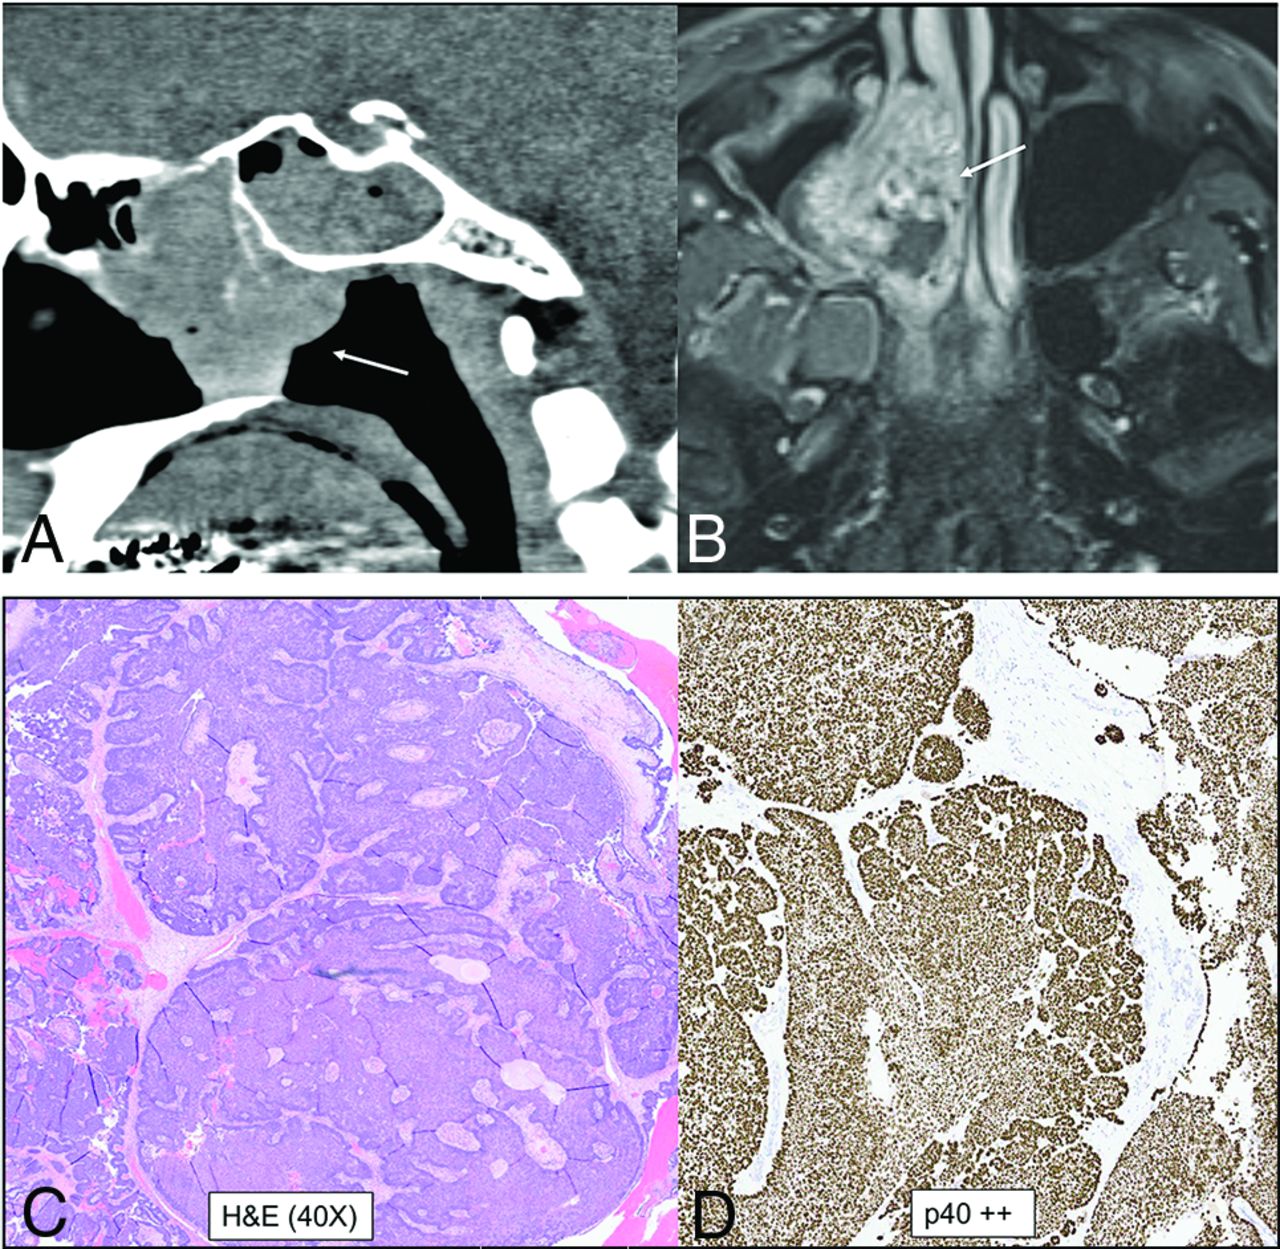

Along similar lines, DEK-AFF2 carcinoma is an emerging entity, currently included as a subtype of nonkeratinizing SCCa, most commonly occurring within the nasal cavity with a peculiar propensity for the posterior part of the middle turbinate (Fig 10). Epidemiologic data on this entity are limited, with the largest series of 13 patients (Rooper et al32) having a median age at presentation of 56 years (range, 18–79 years ). Limited published data on this entity have shown that despite bland histologic features, these carcinomas are clinically aggressive tumors, with a higher risk of recurrence, nodal spread, and metastasis compared with the parent category. DEK-AFF2 carcinomas should be considered in the differential diagnosis of high-grade sinonasal malignancies. This subcategory, however, shows an excellent response to immunotherapy. There is increasing evidence that nonkeratinizing SCCa with DEK-AFF2 is a distinctive tumor entity and serves as a good example of how “poorly differentiated” and “undifferentiated” tumors are being continuously refined.32,33 RNA sequencing is increasingly being performed on multiple sinonasal neoplasms because immunohistochemical assays are not available, especially for newer entities. Finally, there is a newly created section dedicated to genetic tumor syndromes involving the head and neck. The initiative was undertaken to facilitate better understanding of the tumors and associated syndromes and to establish recommendations for monitoring and treating these patients. Many tumors that were thought to be sporadic earlier are now known to be a part of syndrome complex, with identification of specific mutations. A great example of this would be the PTEN germline mutation found in about 85% of patients with Cowden syndrome, characterized by multiple hamartomas involving the oral cavity.1,34

DEK-AFF2 carcinoma. A smooth homogeneous density mass (A, arrow) noted within the posterior ethmoid and nasal cavity with heterogeneous enhancement on MRI (B, arrow). The mass blocks the sphenoethmoidal recess with trapped secretions in the sphenoid sinus. The carcinoma demonstrates classic features of nonkeratinizing SCCa, with blunted papillae and invasion into the stroma as interconnecting ribbons on the H&E stains (C) with infiltrate of inflammatory cells, including lymphocytes and neutrophils. The tumor is diffusely positive for the squamous immunohistochemical marker p40 (D). To evaluate fusion-driven tumor, we performed targeted RNA sequencing, and DEK-AFF2 fusion was found, with breakpoints of DEK (exon 7) and AFF2 (exon 6).